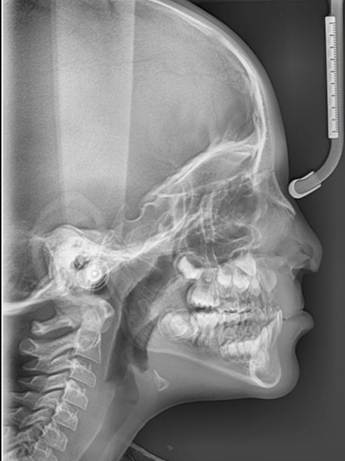

Radiographic Assessment

Radiographic assessment complemented the clinical findings. Panoramic radiography confirmed the congenital absence of the upper left central incisor (tooth 21). A series of periapical radiographs (PA) was obtained to evaluate the presence of radicular lesions, which revealed multiple primary molars requiring pulp therapy (Figure 2).

Figure 2. A) Panoramic Radiograph Showing the Congenital Absence of the Upper Left Central Incisor and the Cleft in the Alveolar Bone, B) Periapical Radiographs (PA) of the Upper Right Quarter, C) PA of the Upper Left Quarter, D) PA of the Lower Left Quarter, E) PA of the Lower Right Quarter